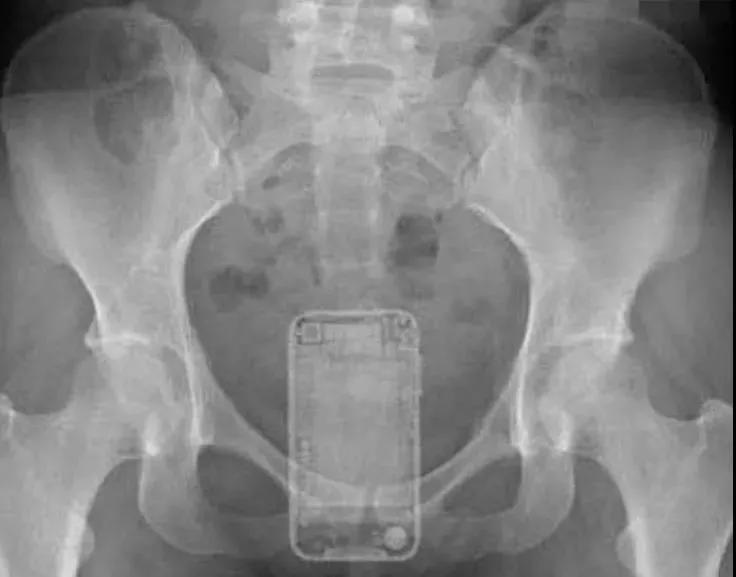

假设你是一位肛肠科医生 完全可以组织一次“直肠异物大赏”

你究竟能认出几种

塞入直肠里的异物“应有尽有”

甚至还有手机,千奇百怪

西南医科大学附属中医医院肛肠科主任李五生教授说:直肠异物是直肠里出现除了粪便以外的其他东西,比如灯泡、按摩棒、玻璃药瓶、陀螺、蜡烛、圆柱形金属瓶等等,甚至常见的蔬菜和长条状的物体,比如黄瓜、火腿肠、茄子、苦瓜、黄鳝、泥鳅……